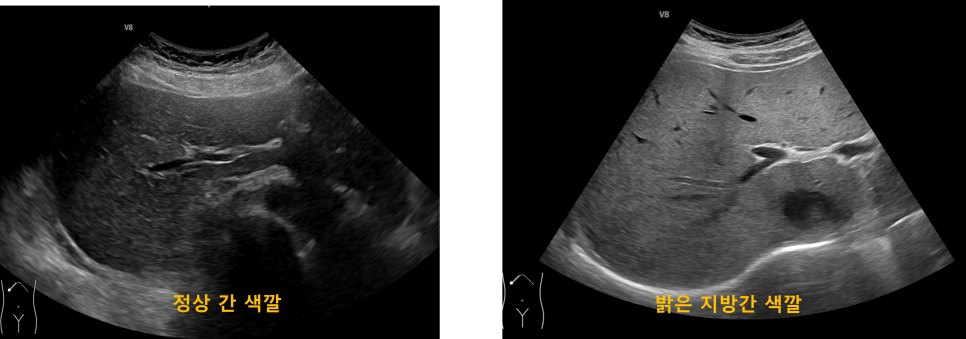

https://adsense.google.com/adsense/u/1/pub-9161951367286286/myads/sites/preview?url=notion6988.tistory.com 🧪 경직도 높은 지방간… 합병증 위험도 높다